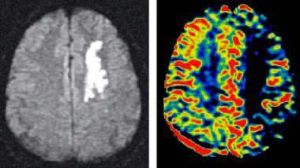

DWI在臨床上主要用於超早期腦缺血診斷的套用:急性腦缺血缺氧造成的主要是細胞毒性水腫,尤其是神經元/膠質細胞細胞毒性水腫,如急性腦梗死、早期壞死灶(未液化者)、缺氧缺血性腦病,在DWI上表現為高信號,與常規SE序列相比,能更早的發現梗塞區的信號異常。需要鑑別注意的是有些腦組織病變在DWI上也表現為高信號,如多發硬化的活動病灶、Wallerian變性,如髓鞘內(裂)水腫(神經髓鞘細胞水腫),進行性多灶性腦白質病,胺基酸代謝異常(如苯丙酮尿症等),透神經元性變性、軸索水腫及部分腫瘤、血腫、膿腫等。其他臟器也可行DWI檢查,但目前在這些方面的經驗還不多,需要進一步研究。